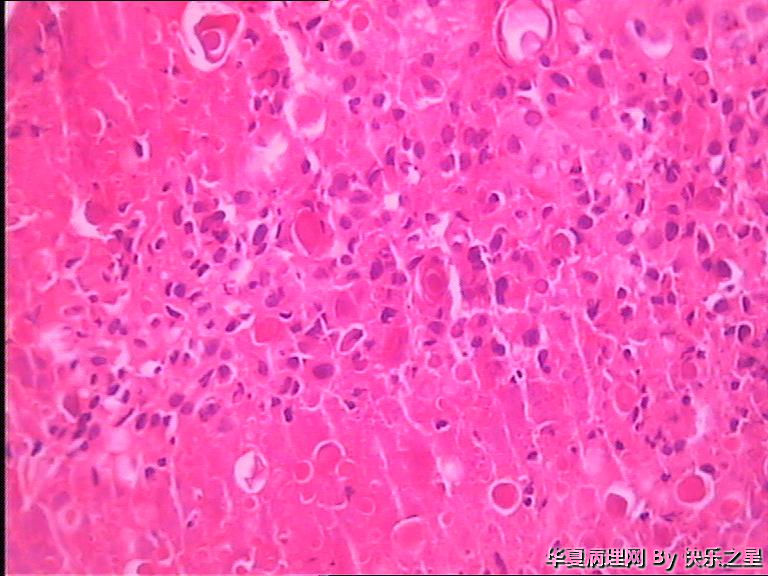

女,32岁,右足第一趾骨头疼痛5天。

肉芽肿性炎伴砂粒体形成。可能为深部真菌感染引起。异物性肉芽肿和腱鞘巨细胞瘤也可以这样。总之是良性瘤样病变。

痛风石?